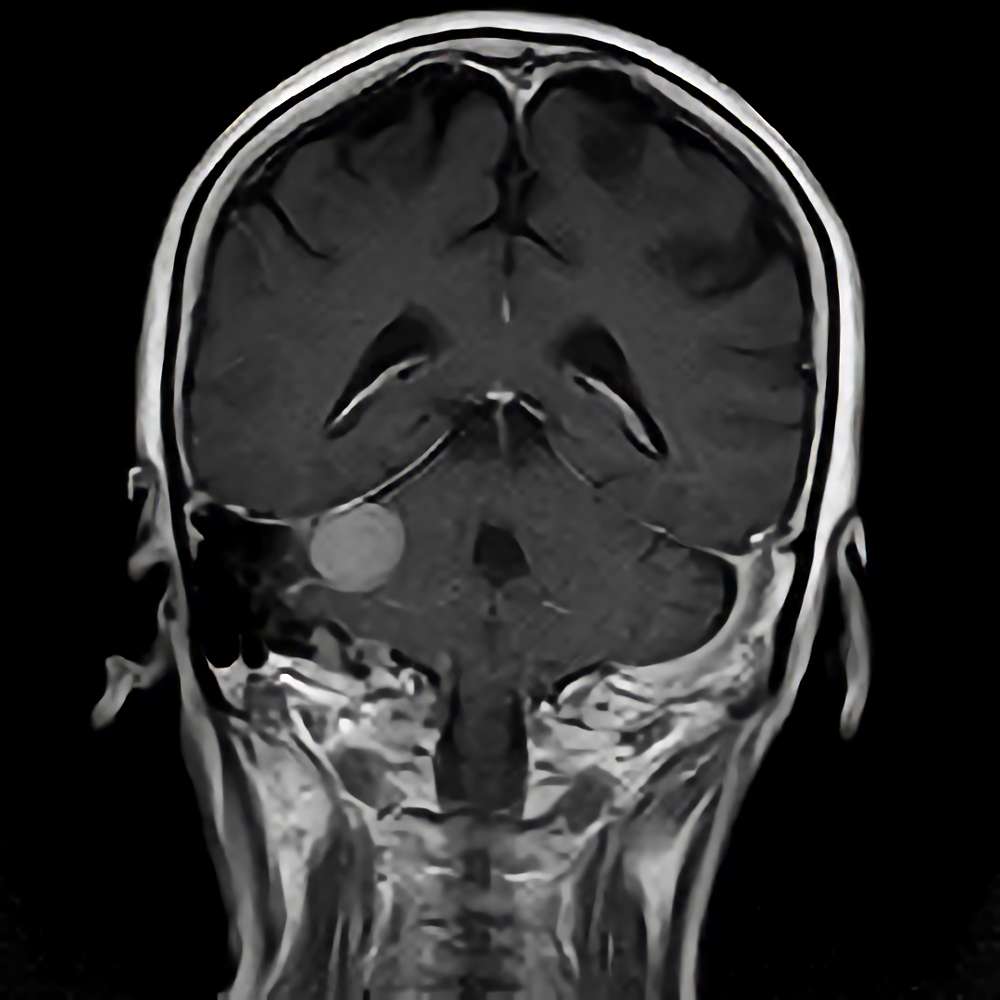

手術前2